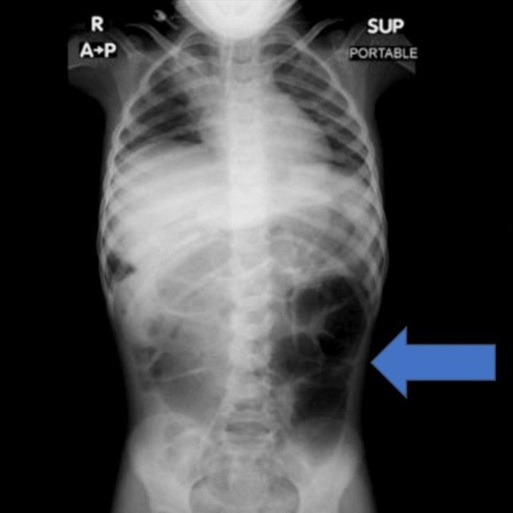

여아는 복통과 소화장애 증상을 몇 주간 반복해 겪었다. 결국 여아는 병원에 방문해 정밀검사를 진행했고, 의료진은 아이의 위 내부에 비정상적으로 큰 이물질이 자리한 것을 확인했다.

수술을 통해 제거된 물질의 정체는 다량의 머리카락이 엉킨 덩어리였다. 머리카락 뭉치는 위에 머무는 데 그치지 않고 소장 일부까지 길게 이어진 상태였던 것으로 전해졌다.